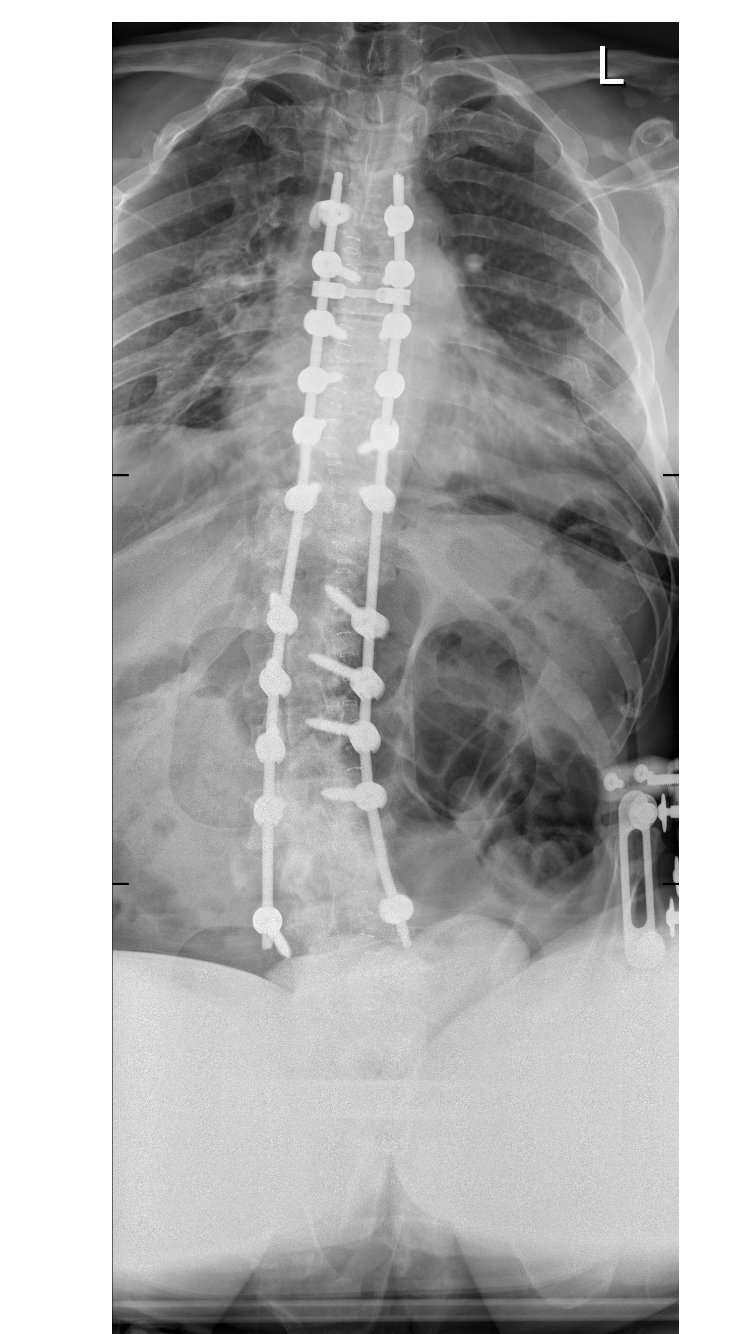

A shame that they have come apart!